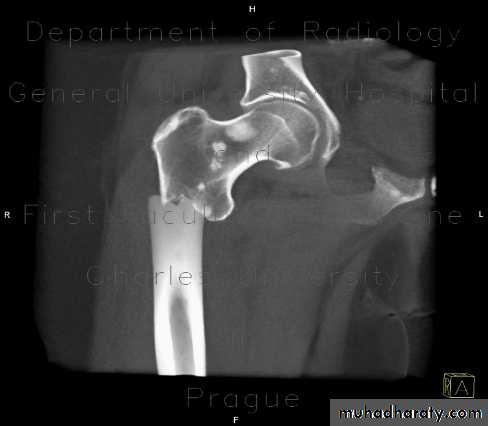

4. Pathological fractures

Fractures may occur even with normal stresses if the bone has been weakened by a disease that cause changes in its structure.The underlying disease may be local (bone cyst). Or generalized disorder affecting several bones or whole skeleton e.g. osteogenesis imperfecta or Paget’s disease.

Indication for internal fixation:

Unreduced fractures

Unstable fractures

Fractures that unit poorly or slowly ( femoral neck)

Pathological fractures

Multiple fractures

Fractures in a who present nursing difficulties (paraplegic, multiple injuries, elderly)